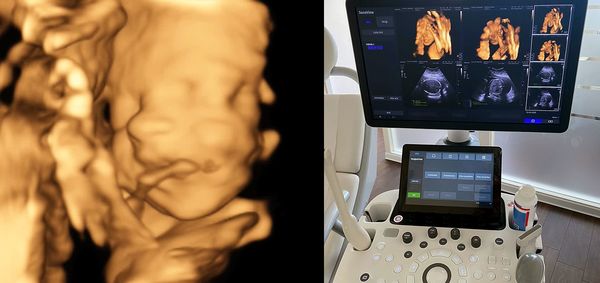

- Ultraschall in der Schwangerschaft – neben den 3 Screening-Ultraschallen in der Schwangerschaft gibt es einen frühen Fehlbildungsultraschall mit Messung der Nackenfalte in den 13./14. Schwangerschaftswoche und zusätzliche Ultraschalluntersuchungen, mit deren Hilfe bei Nicht-Risiko-Schwangerschaften die Entwicklung des ungeborenen Kindes überwacht werden kann. Zusätzliche Informationen liefert der 3D/4D Ultraschall mit dreidimensionalen plastischen Bildern des Kindes und daneben auch die entstandenen Videosequenzen per USB Stick für zu Hause.

Moderne 3D/4D Ultraschalluntersuchungen -